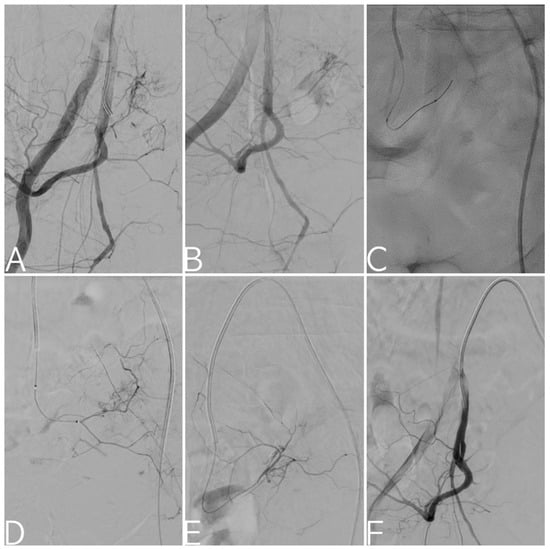

| Bleeding on XA | |

| - No (blind embolization) | 6 (5.2%) |

| - Yes (targeted embolization) | 110 (94.8%) |

| Site of bleeding | |

| - Internal iliac artery (uni-/bi-lateral) | 104 (89.7%)–(62.1%/27.6%) |

| - External iliac artery | 6 (5.2%) |

| - Internal AND external iliac arteries | 6 (5.2%) |

| Main bleeding vessel | |

| - Superior gluteal | 36 (31%) |

| - Iliolumbar | 17 (14.6%) |

| - Lateral sacral | 5 (4.3%) |

| - Inferior gluteal | 6 (5.2%) |

| - Superior vesical | 5 (4.3%) |

| - Inferior vesical/vaginal | 4 (3.4%) |

| - Middle rectal | 6 (5.2%) |

| - Internal pudendal | 14 (12.1%) |

| - Obturator | 13 (11.2%) |

| - Others (e.g., uterine, ext. iliac branches, etc.) | 10 (8.7%) |

| Number of embolized vessels | 1.4 (±0.5) |

| Type of angioembolization | |

| - Prophylactic (uni-/bi-lateral) | 60 (51.7%) |

| - Distal | 56 (48.3%) |